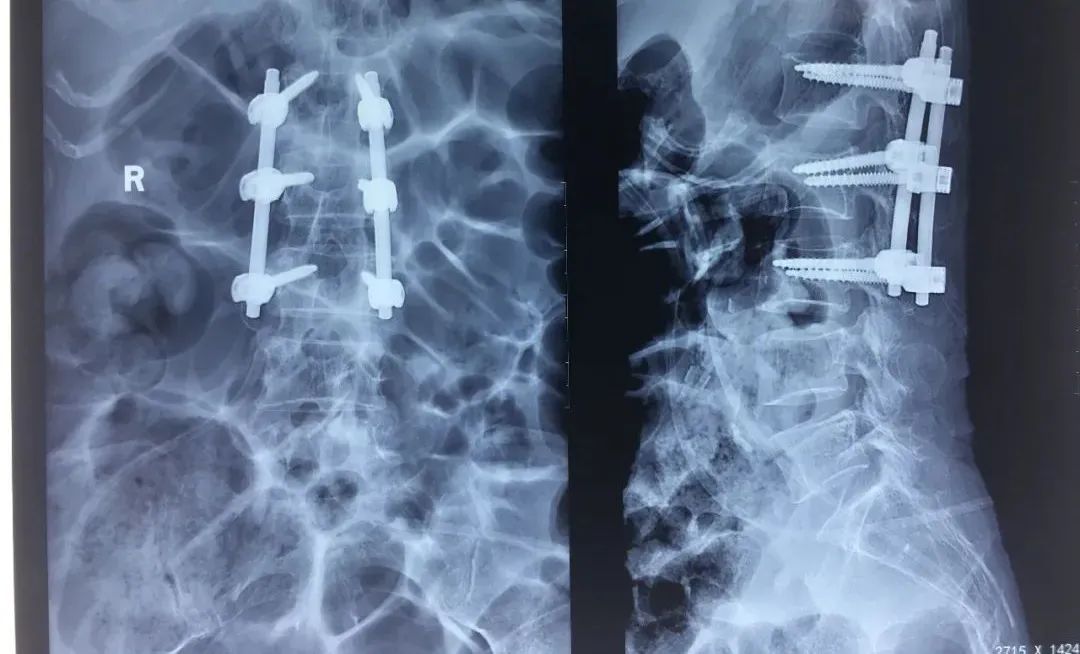

完善术前检查后,在手术麻醉科的大力支持下,2月13日09点30分,由赵学刚携团队为患者施行了腰2椎体压缩性骨折切开复位内固定术,半个小时,手术顺利完成。

手术第一天,王阿姨就可以在医护人员的协助下坐起自主进食,顺利下床,在病房的走廊散起步来。